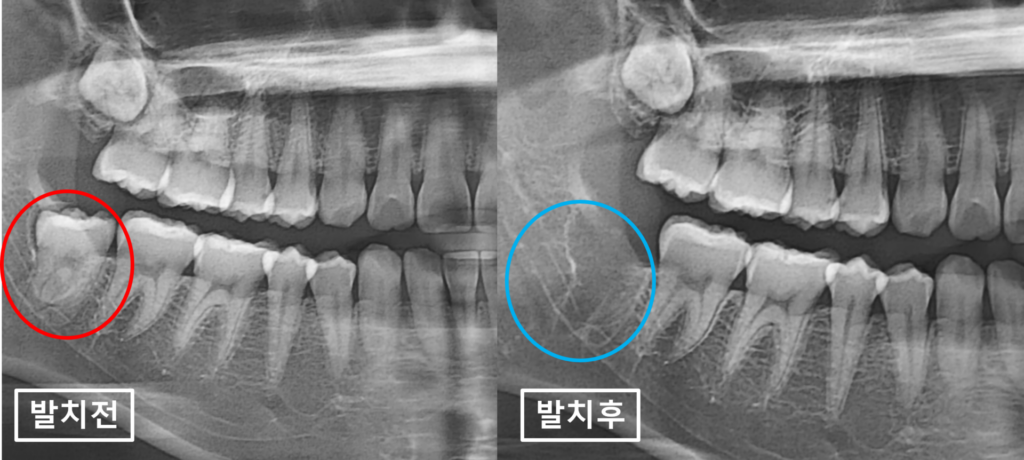

24.03.09(초진) / 24.03.11(치료 후) – 57y 박OO님

환자분께는 의뢰주신 선생님,

그리고 저역시도

현재 나타난 원인모를 치통이

매복사랑니의 염증에 의한 것인 것 같고

매복사랑니를 발치하고 증상이 어떤지

지켜보자고 말씀드렸습니다.

다행히

발치 후 치통은 사라졌고

위에서 설명드린 매복사랑니 발치 후

정말 간혹 나타날 수 있는

설신경 손상 역시 없었습니다.

다행이네요.